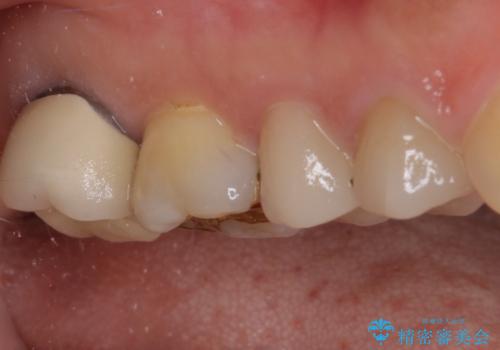

ゴールドインレーは銀歯のインレーやセラミックインレーと比べ、「技工操作の精度が高く、適合が著しく良い」というメリットがあります。特に上の奥歯は歯科医師の操作が行いにくいため、「適合の良さ」は再治療のリスクを防ぐ上でとても重要な要素となります。

上の奥歯は金属色が見えることもないため、審美的な問題は全くありません。

咬合力が原因と思われるむし歯治療では、ゴールドインレーが第一選択になるといっても良いかもしれません。